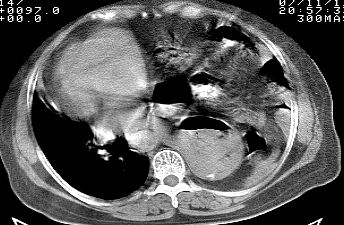

标题: CT10753:女, 64岁 隔疝 [打印本页]

标题: CT10753:女, 64岁 隔疝

女, 64岁 三十年前胸部外伤史, 间断胸闷,

典型左侧膈疝,疝出物为胃和大网膜,纵隔右移

同意左侧膈疝,不过,有过外伤史,左肺有受压征象,同时有胸膜增厚。